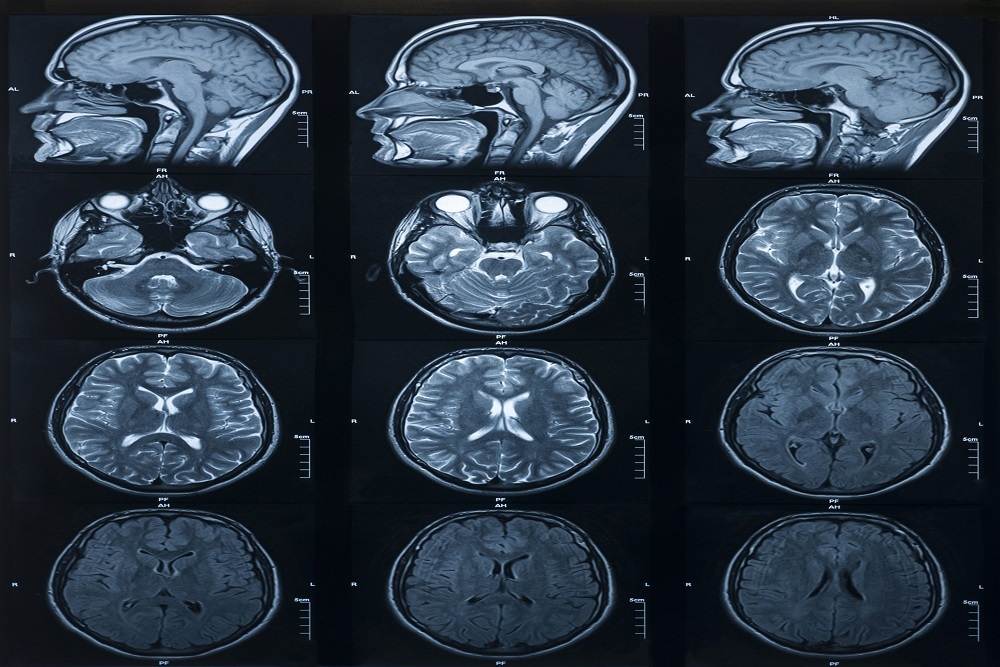

The incidence of glioblastoma, the most common brain cancer, is rising and its prognosis remains dismal, with a median survival of 12 to 15 months. Surgical removal of all or part of a tumor—known as resection—remains the first line of treatment, with additional radiation and temozolomide treatment leading to modest improvement in overall survival.

Treatment of brain tumor patients is expensive, often involving ineffective treatments and repeat biopsies. Removing the cancerous tumor tissue while preserving normal tissue in the brain is challenging. Better surgical resection of brain tumors doubles a patient’s survival rate.

However, surgeons can’t always determine the edges of the tumor. And high-grade brain tumors are often invasive, with small tentacle-like projections that extend from the main tumor mass and are invisible to the naked eye.

“It is these tumor cells that lead to greater than 90% recurrence in patients due to tumor cells left at the edge of the primary tumor,” Sloan said. “Therefore, better visualization of invading tumor cells improves survival and is an important unmet clinical need.”